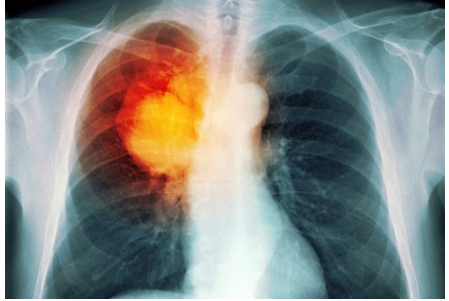

Trong hầu hết các trường hợp, khi bác sĩ nghi ngờ bệnh nhân mắc ung thư phổi với các triệu chứng điển hình như ho mãn tính hoặc thở khò khè, lúc đó, bác sĩ sẽ cho người bệnh đi chụp X-quang hoặc các xét nghiệm hình ảnh khác. Bệnh nhân cũng có thể được yêu cầu xét nghiệm đờm. Nếu một trong các xét nghiệm cho thấy xuất hiện dấu hiệu của ung thư, bước tiếp theo bác sĩ sẽ tiến hành sinh thiết phổi.

Có hai loại chính của ung thư phổi là ung thư phổi tế bào nhỏ và ung thư phổi không phải tế bào nhỏ. Ung thư phổi tế bào nhỏ là loại ung thư phát triển nhanh, nó có thể lây lan nhanh đến các bộ phận khác của cơ thể. Loại ung thư này thường xuất hiện ở người sử dụng thuốc lá và hiếm thấy ở người không hút thuốc. Ung thư phổi không phải tế bào nhỏ phát triển chậm hơn và phổ biến hơn, đây là loại ung thư ít xâm lấn hơn loại trên. Trong các bệnh ung thư phổi có đến 85% những người ung thư phổi thuộc loại ung thư không tế bào nhỏ. Loại ung thư này nếu phát hiện sớm, phẫu thuật, xạ trị hay hóa trị có thể chữa khỏi căn bệnh này.

Mỗi loại ung thư phổi có cách xâm lấn khác nhau trong cơ thể. Như ung thư phổi tế bào nhỏ được chia thành hai giai đoạn: Giai đoạn giới hạn có nghĩa là ung thư được giới hạn trong một phổi và các hạch bạch huyết có thể ở gần vị trí khối u. Giai đoạn ung thư lan rộng có nghĩa là ung thư đã lan rộng khắp phổi hoặc ra các bộ phận khác. Ung thư phổi không phải tế bào nhỏ được chia thành từ 1 đến 4 giai đoạn, tùy thuộc vào việc khối u lan rộng đến đâu.